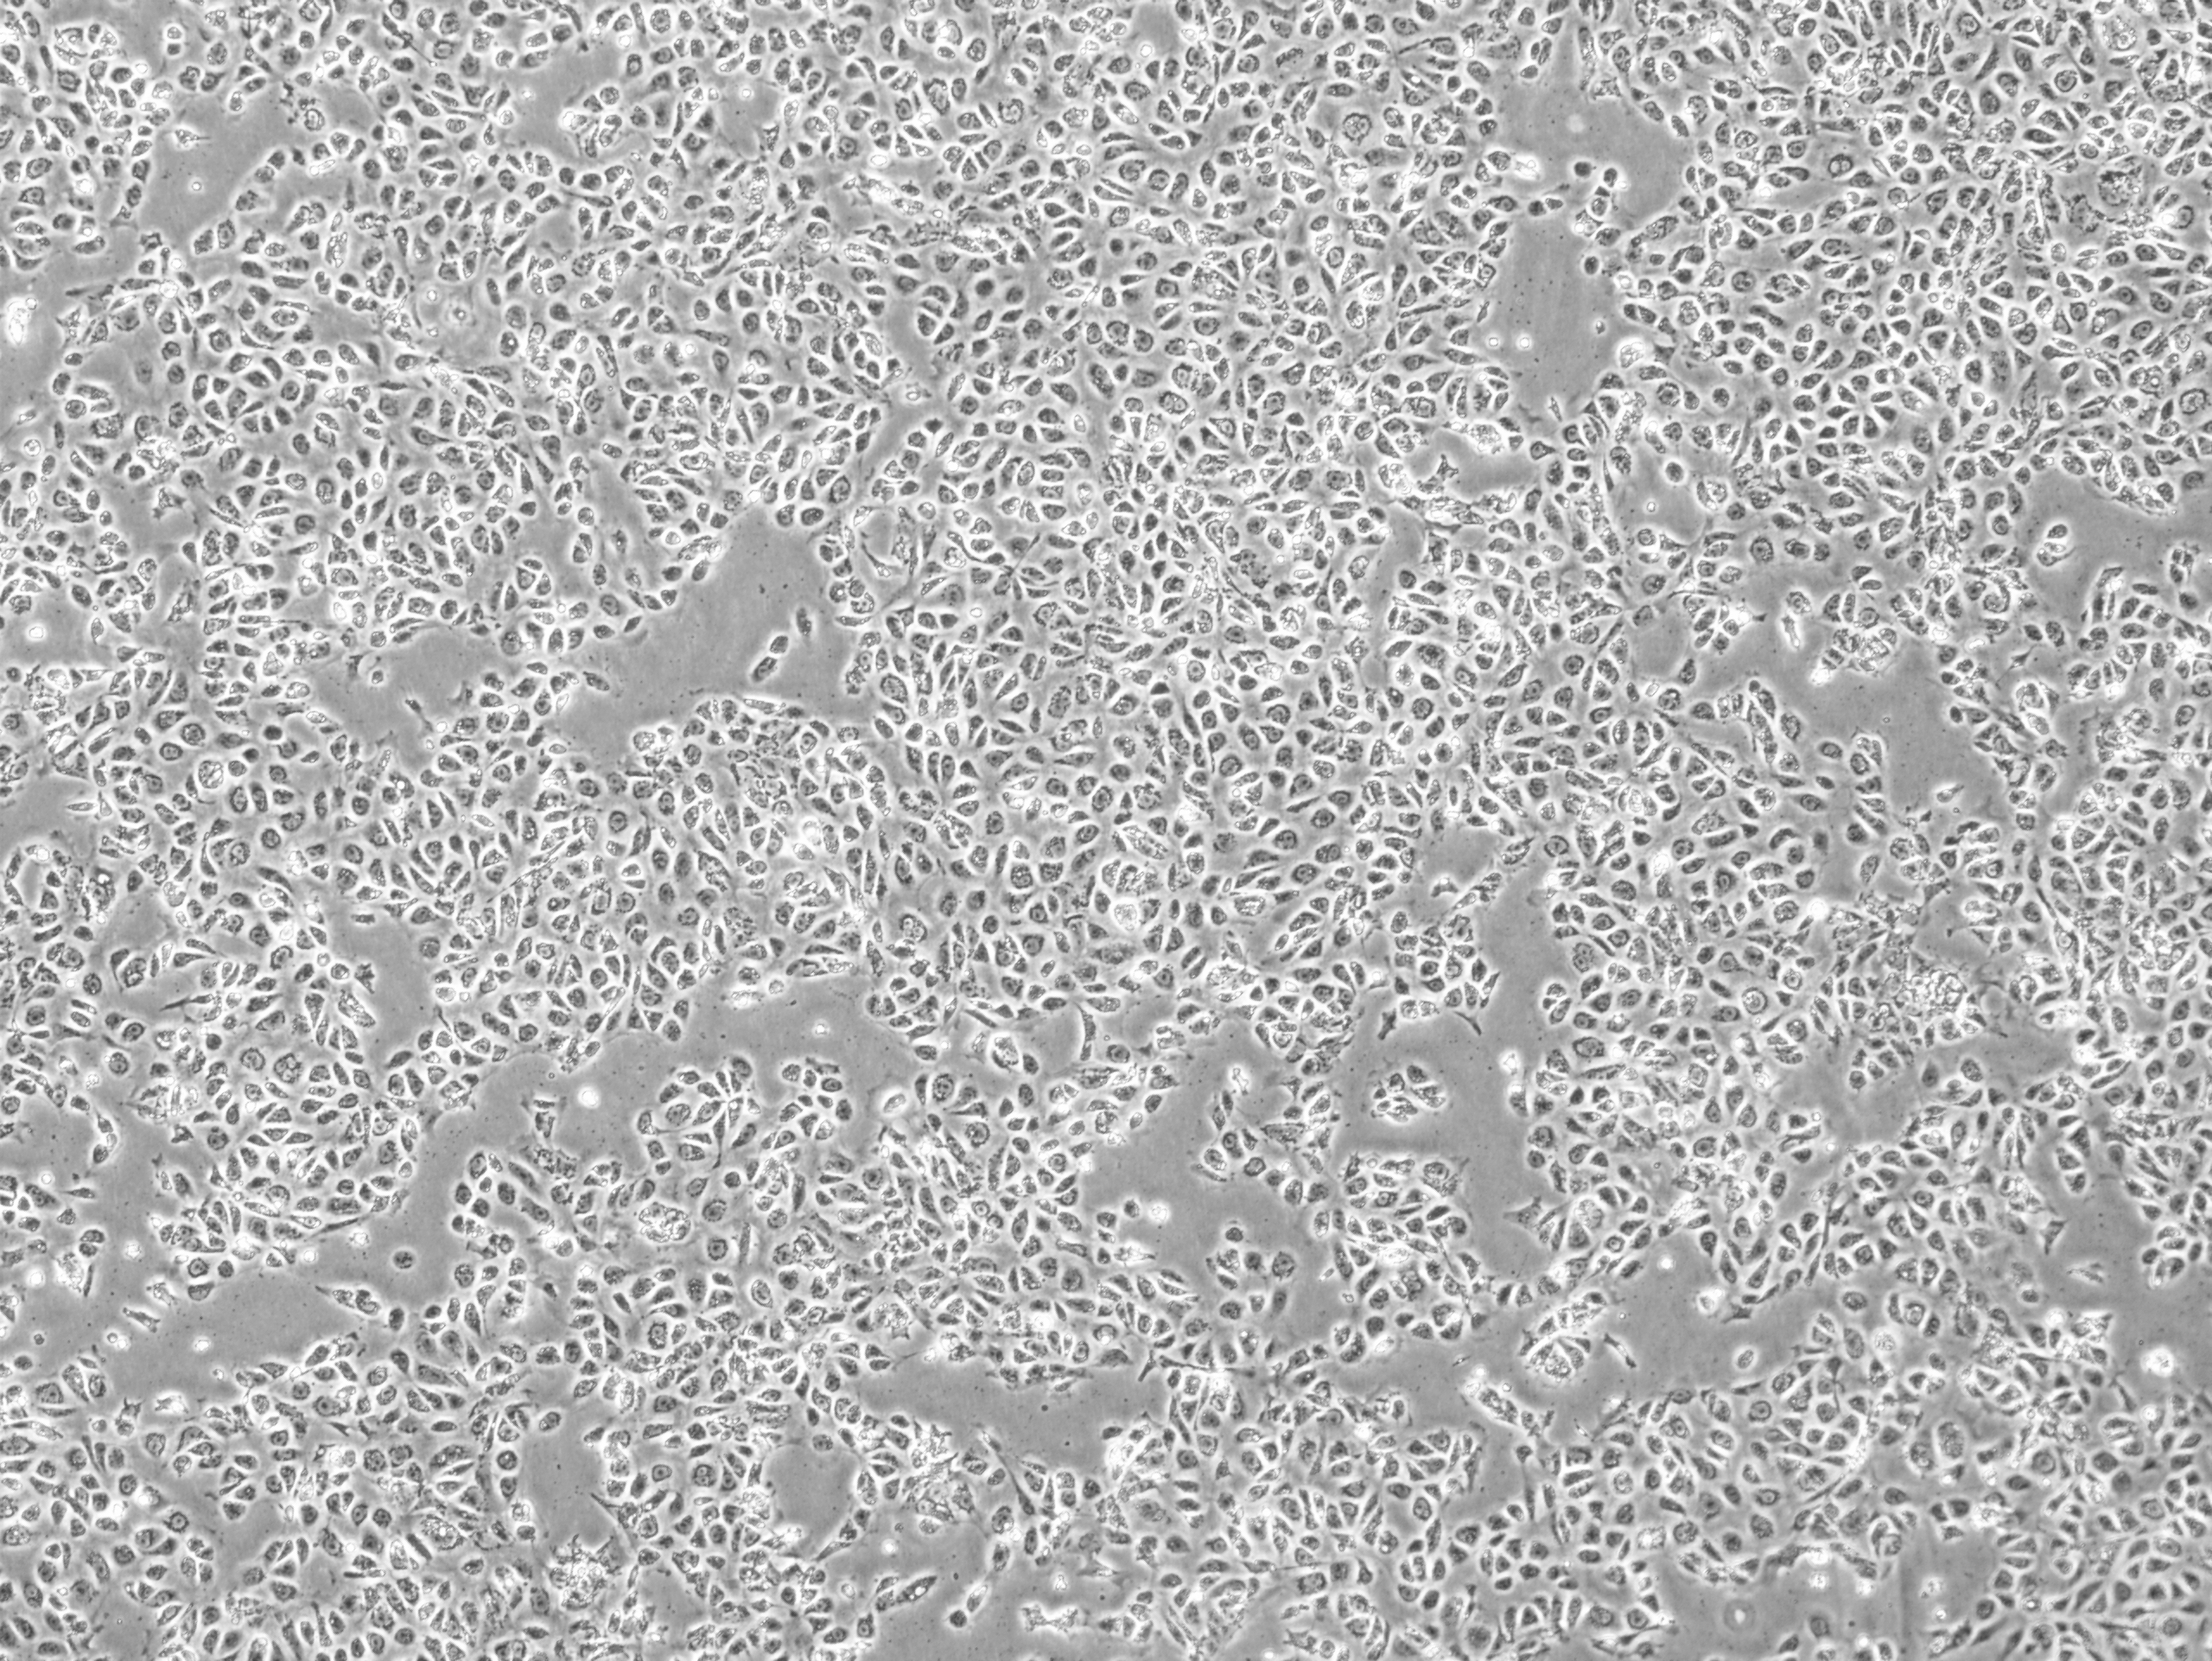

The collaboration is set to accelerate the development of Karis Bio’s innovative autologous iPSC-derived endothelial cell (iPSC-EC) therapy designed to generate new blood vessels in ischemic organs. Karis Bio’s first-in-human clinical study in South Korea leverages patient-specific iPSCs to restore blood flow and repair damaged tissues, offering patients a revolutionary alternative to conventional invasive procedures such as stents or bypass surgery, while eliminating the risk of immune rejection.

Cellino’s Nebula™ platform will enable scalable, high-quality production of autologous iPSCs, accelerating Karis Bio’s path to commercial scale. The Nebula™ platform is a closed-cassette, advanced biomanufacturing system that is both autonomous and deployable at the point of care, ensuring robust, reproducible, and contamination-free production. The initial phase of the collaboration focuses on industrializing autologous iPSC manufacturing, with plans to expand into Phase 2 trials through Karis Bio, USA (headquartered in Atlanta) in the U.S.